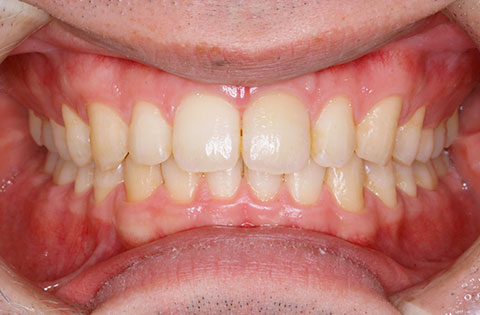

矯正前 正面

矯正後 正面

主訴 正中が開いている。咬み合わせが深く歯肉を咬んでしまう。

年齢 20代

治療法 上下顎マルチブラケット装置

抜歯の有無 なし

治療期間 1年6ヶ月